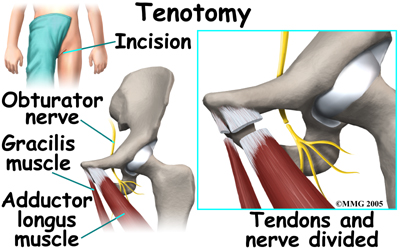

Sometimes, adequate motion cannot be regained with traction and Chiropractic alone, therefore in some cases, surgery will be required to obtain adequate containment. If the condition is longstanding, the muscles may have contracted or shrunk and cannot be stretched back out. To help restore motion, the surgeon may recommend a tenotomy of the contracted muscles. When a tenotomy is performed, the tendon of the muscle that is overly tight is cut and lengthened. This is a simple procedure that requires only a small incision. The tendon eventually scars down in the lengthened position, and no functional loss is noticeable.

Surgical treatment for containment usually consists of procedures that realign the femur (thighbone), the acetabulum (hip socket), or both.